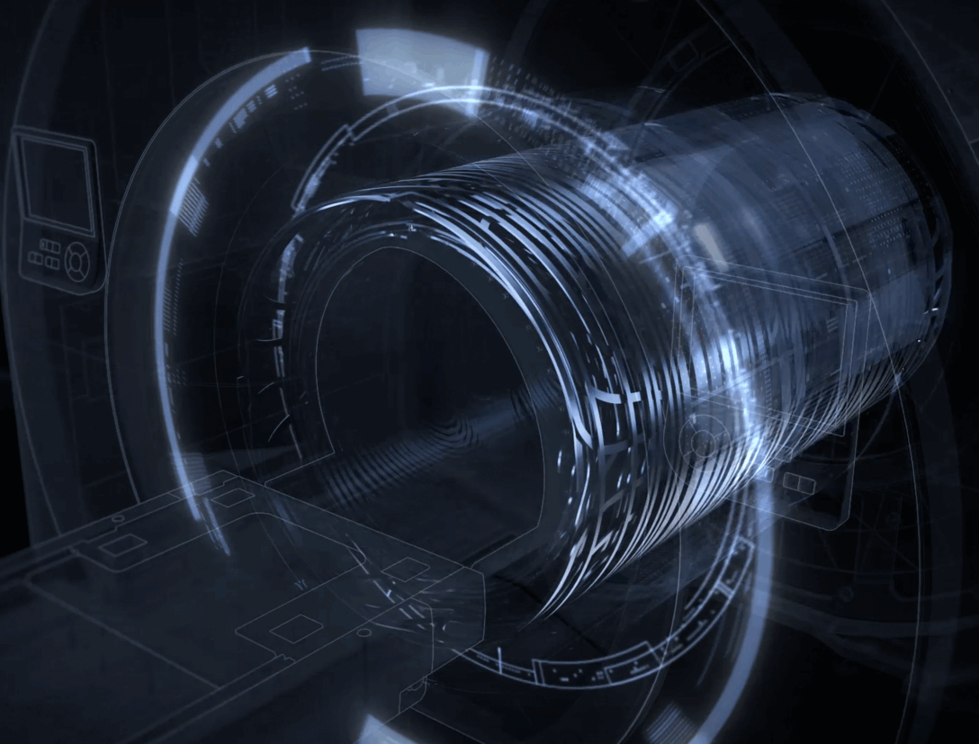

「3.0T级」高性能射频

uMR 680突破传统射频接收架构限制,支持独立72+通道射频接收平台,构建起真正的超高通道、超高速全数字传输通路,同时,基于AI深度学习图像重建技术的完美融合,从数据采集、数据传输、数据运算、数据重建全链条赋能,让高清影像轻松可得。